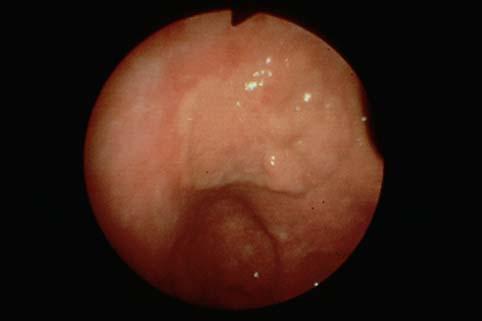

疾患(病理主体)の分類悪性上皮性腫瘍/腺癌

部位(臓器別)胃(部位)/体部

検査方法内視鏡

腫瘍の肉眼分類0型(表在型)/IIc型(IIc+IIa)

病変の最大径(ミリ)30〜34

腫瘍の深達度sm